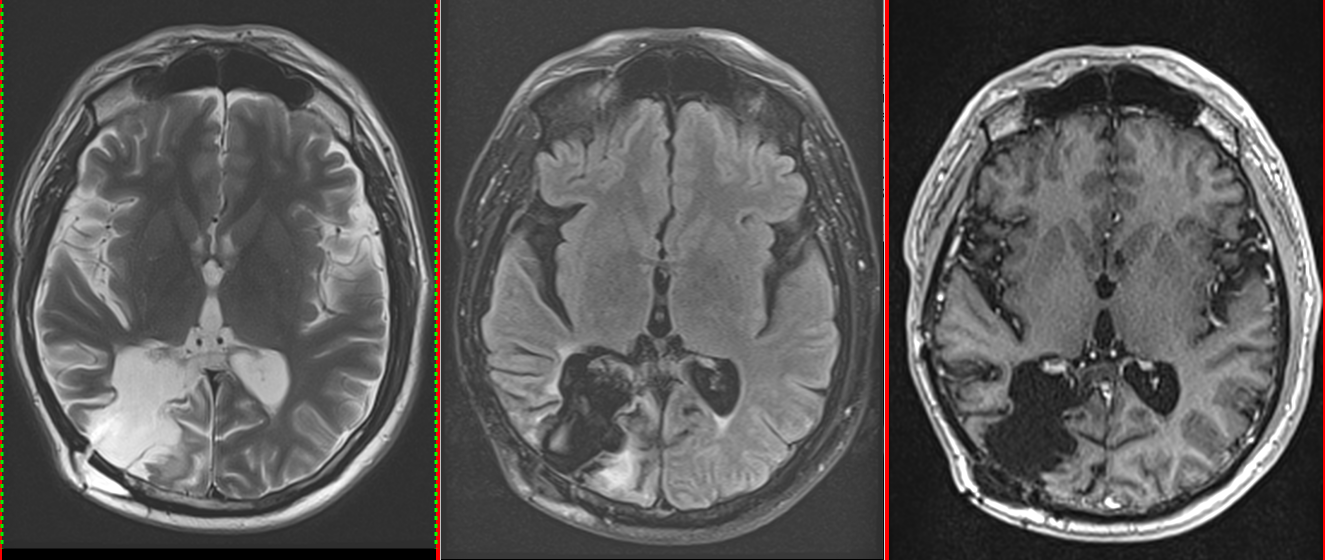

• RMN cerebral este metoda de elecție. Tumora apare ca o leziune hipointensă în T1 și hiperintensă în T2/FLAIR, cu captare neregulată de contrast.

• Constant se observă edem peritumoral și efect de masă.

Astrocitom anaplazic (grad III) temporal drept – RMN preoperator